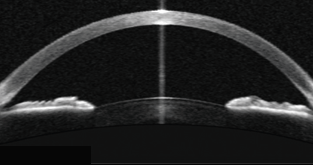

- CORNEA

- IRIDOCORNEAL ANGLE

- CE - corneal epithelium

- ICA - iridocorneal angle

- TM - trabecular meshwork

- SC - scleral spur

- SS - Schlems canala

- IPE - iris pigment epithelium

- SL - sclera

- IS - iris